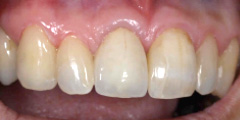

オールセラミック クラウン症例

オールセラミックの最大の利点は光の透過や反射が自然で、現在のクラウンでは最も審美性に優れています。材料学的に生体親和性、科学的安定が高く、着色、変色しないなど、お口の中で経年的に安定した物性を有します。また、物性的にも高強度型セラミック材料の開発により、力学的強度が著しく向上し、臨床的信頼も高まっております。